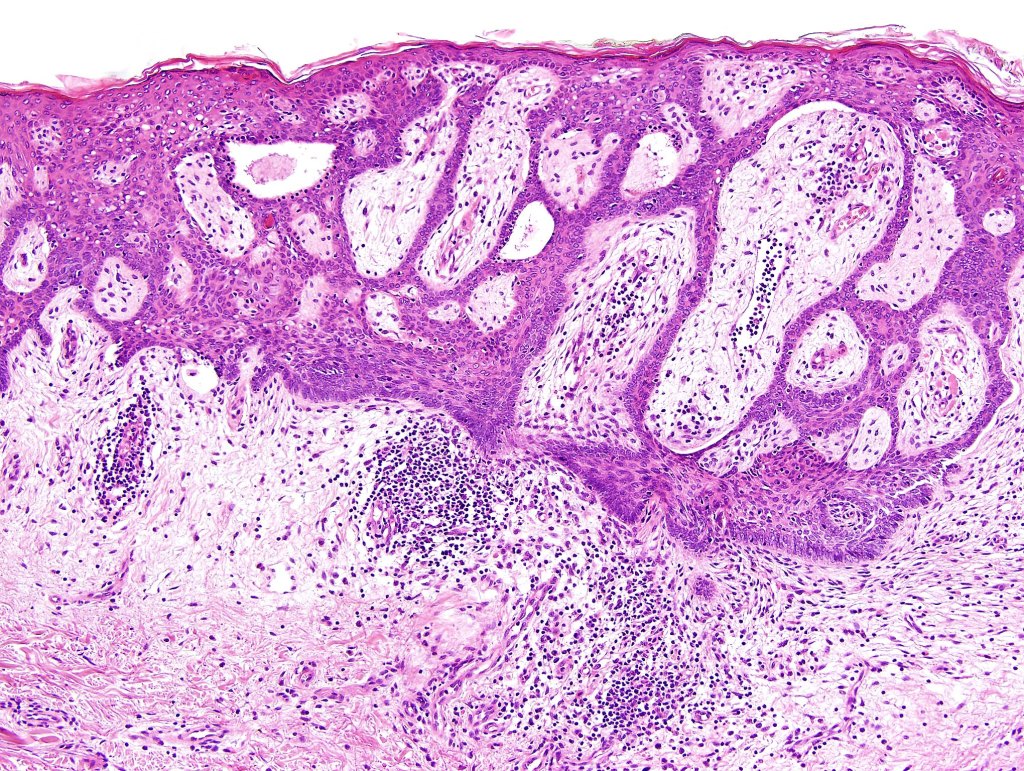

Histological features

•Characteristic fenestrated epithelial plate-like silhouette suspended below the epidermis

•Pale-staining epithelial cells with peripheral palisading

•Eosinophilic basement membrane

•No pleomorphism or mitotic activity